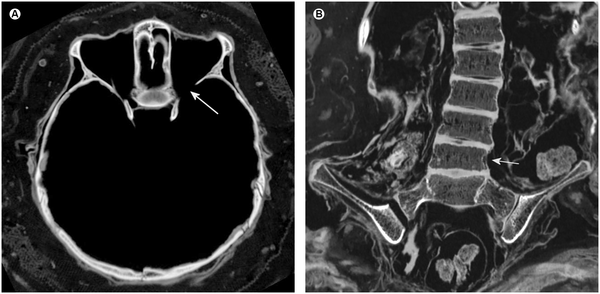

Тело не было специально мумифицировано: внутренние органы оставлены на месте, нет следов обработки бальзамическим составом. Вероятно, мумификация произошла просто за счет высыхания в жарком сухом климате. Тем не менее почти все внутренние органы, мягкие ткани головы и опорно-двигательной системы хорошо сохранились. Их изучение показало, что при жизни ребенок сильно болел: нейрофриброматоз I типа, болезнь Шагаса, и, вероятно, туберкулез. Эти болезни в Империи инков были в то время широко распространены, из-за чего половина детей не доживала до 15 лет. Кроме того, скудное количество подкожного жира указывает на довольно высокую степень истощения.

Однако смерть ребенка, скорее всего, была вызвана не болезнями. Томографическое обследование показало множественные насильственные повреждение скелета и мягких тканей: перелом шейных позвонков, большеберцовой и левой плечевой кости, разрез на груди, смещение печени за пределы брюшной полости, смещение некоторых зубов. Откуда появились такие серьезные травмы? Образовались ли они уже после смерти мальчика, было ли это убийство, следствие катастрофы или обряда жертвоприношения — неизвестно.